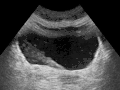

-

Ultrasound showing a jet of urine entering the bladder (large black section) through the ureter